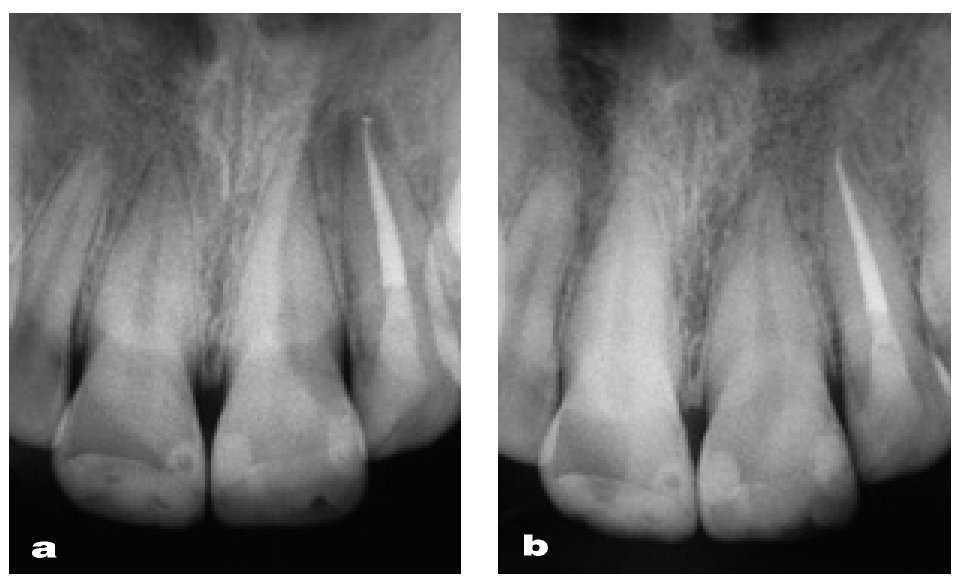

Figura 51 Control radiográfico de las restauraciones y la endodoncia (a) y control radiográfico de las restauraciones dos años después del tratamiento (b) con resolución de la imagen periapical translúcida.